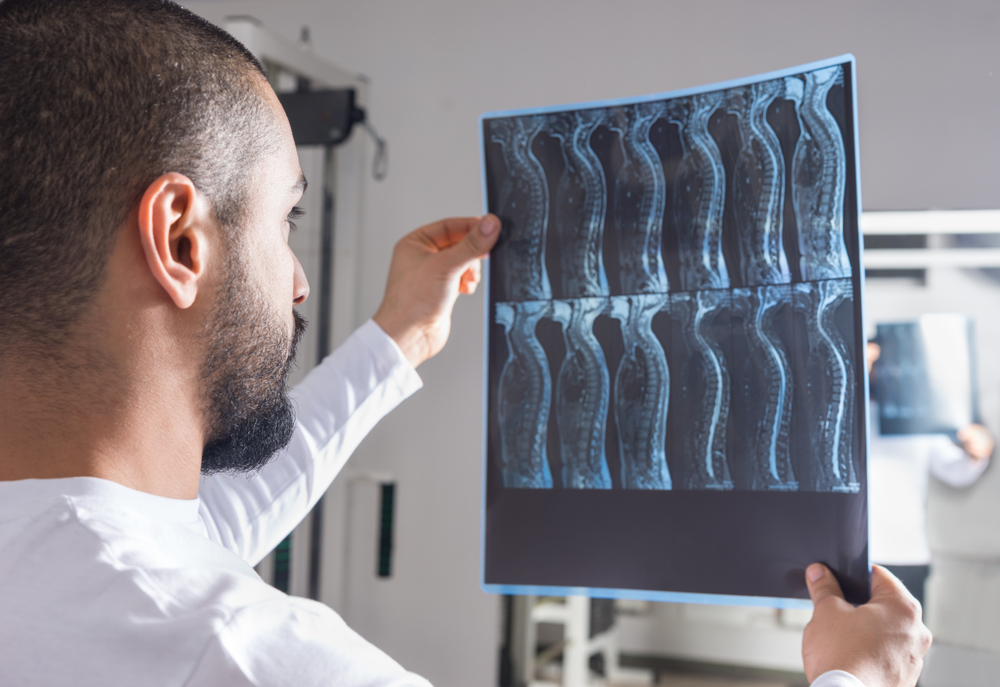

Профессиональные заболевания рентгенологов: риски и профилактика

Раздел: Путеводитель по жизни